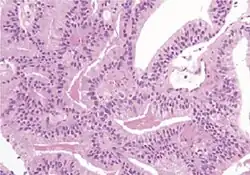

-

Acinar adenocarcinoma with multiple nucleoli. -

Acinar adenocarcinoma with double and eccentric nucleoli.